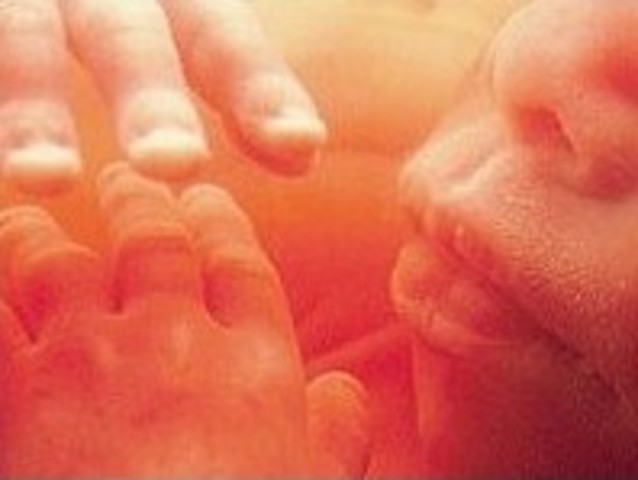

• Week Twenty Six

Week Twenty Six

This is about the time when the fetus becomes most active. The fetus's hands are active and muscle coordination is such that it can suck its thumbs.